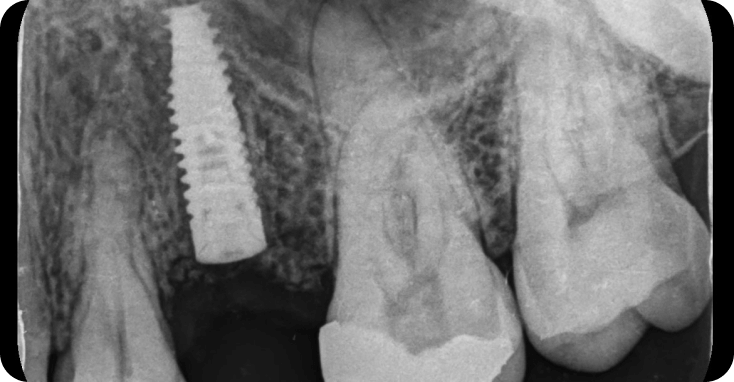

Casos